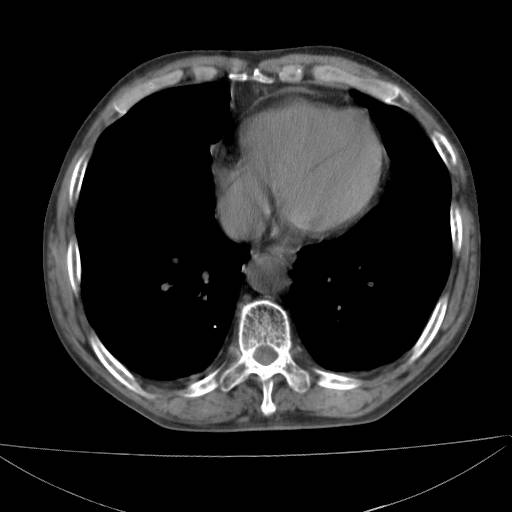

以下是引用zjzjr在2006-12-6 19:04:00的发言:[br]左肺上叶尖后段可见椭圆形高密度影,其内可见点状钙化影,周围可见卫星病灶.首先考虑结核,双侧少量胸腔积液.

以下是引用李世军在2006-12-6 19:54:00的发言:[br]左肺上叶尖后段可见椭圆形高密度影,其内可见点状钙化影,周围可见卫星病灶.首先考虑结核,双侧少量胸腔积液. [br] [br] 双肺轻度肺气肿,左肺上叶后段见多发斑片状密度增高影,周围见少许斑点状卫星病灶,双侧胸膜增厚粘连,纵隔内未见明显改变,考虑结核可能性大,请结合临床或增强扫描. [br] [br]

以下是引用13081830109在2006-12-6 19:35:00的发言:[br]左肺上叶尖后段可见椭圆形高密度影,其内可见点状钙化影,周围可见卫星病灶.首先考虑结核,双侧少量胸腔积液.

以下是引用守望可可西里在2006-12-7 0:01:00的发言:[br][quote]以下是引用zjzjr在2006-12-6 19:04:00的发言:[br]左肺上叶尖后段可见椭圆形高密度影,其内可见点状钙化影,周围可见卫星病灶.首先考虑结核,双侧少量胸腔积液.